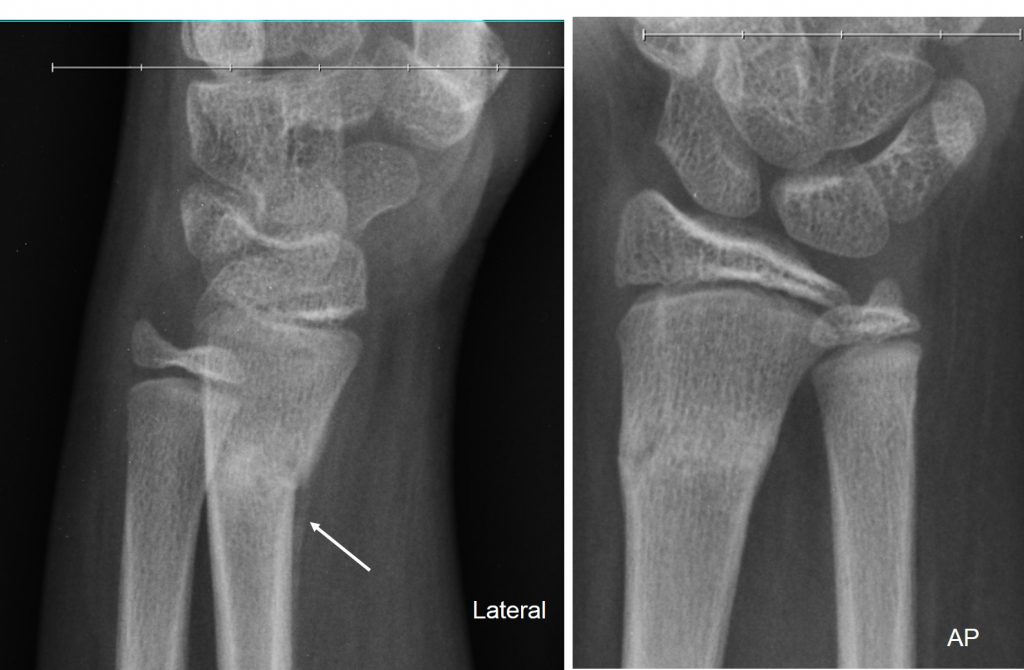

Torus Fracture-Radius - Sumer's Radiology Blog

Torus Fracture-Radius - Sumer's Radiology Blog sumerdoc.blogspot.com

torus fracture radius radiology bone